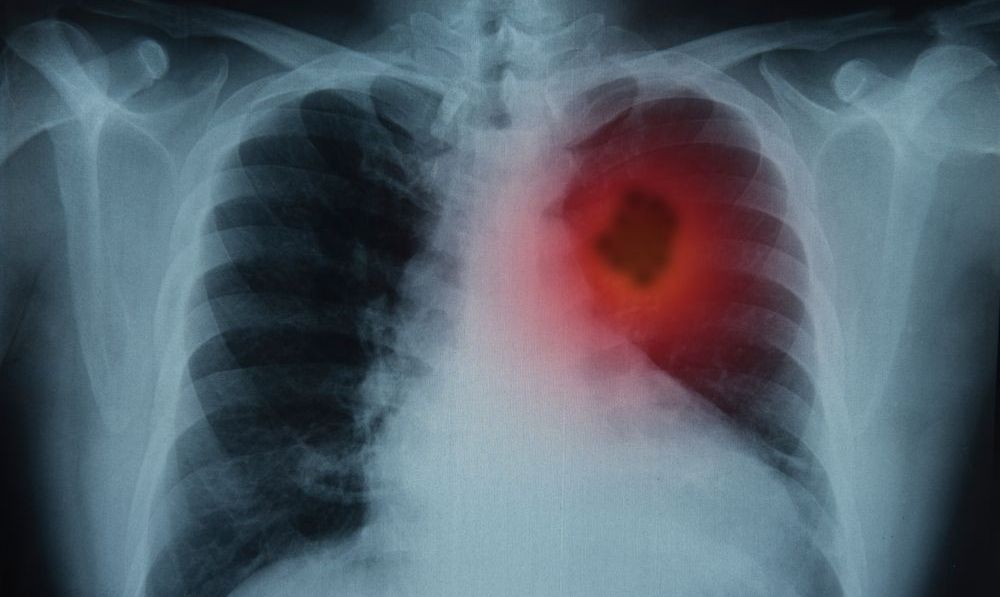

El cáncer de pulmón es el más letal en EEUU.

El cáncer de pulmón es el más letal en EEUU. Crédito: Shutterstock

El tipo de cáncer que más hombres y mujeres mata en Estados Unidos es el cáncer de pulmón. Uno de los principales problemas de esta enfermedad es que es diagnosticado tardíamente, cuando la enfermedad ha avanzado tanto que ya afecta a otros órganos.

La manera más eficaz de detectar el cáncer de pulmón es realizar una tomografía computarizada con dosis bajas. Se trata de una prueba una máquina de rayos X que explora el cuerpo a través de bajas dosis de radiación para generar fotos detalladas de los pulmones.